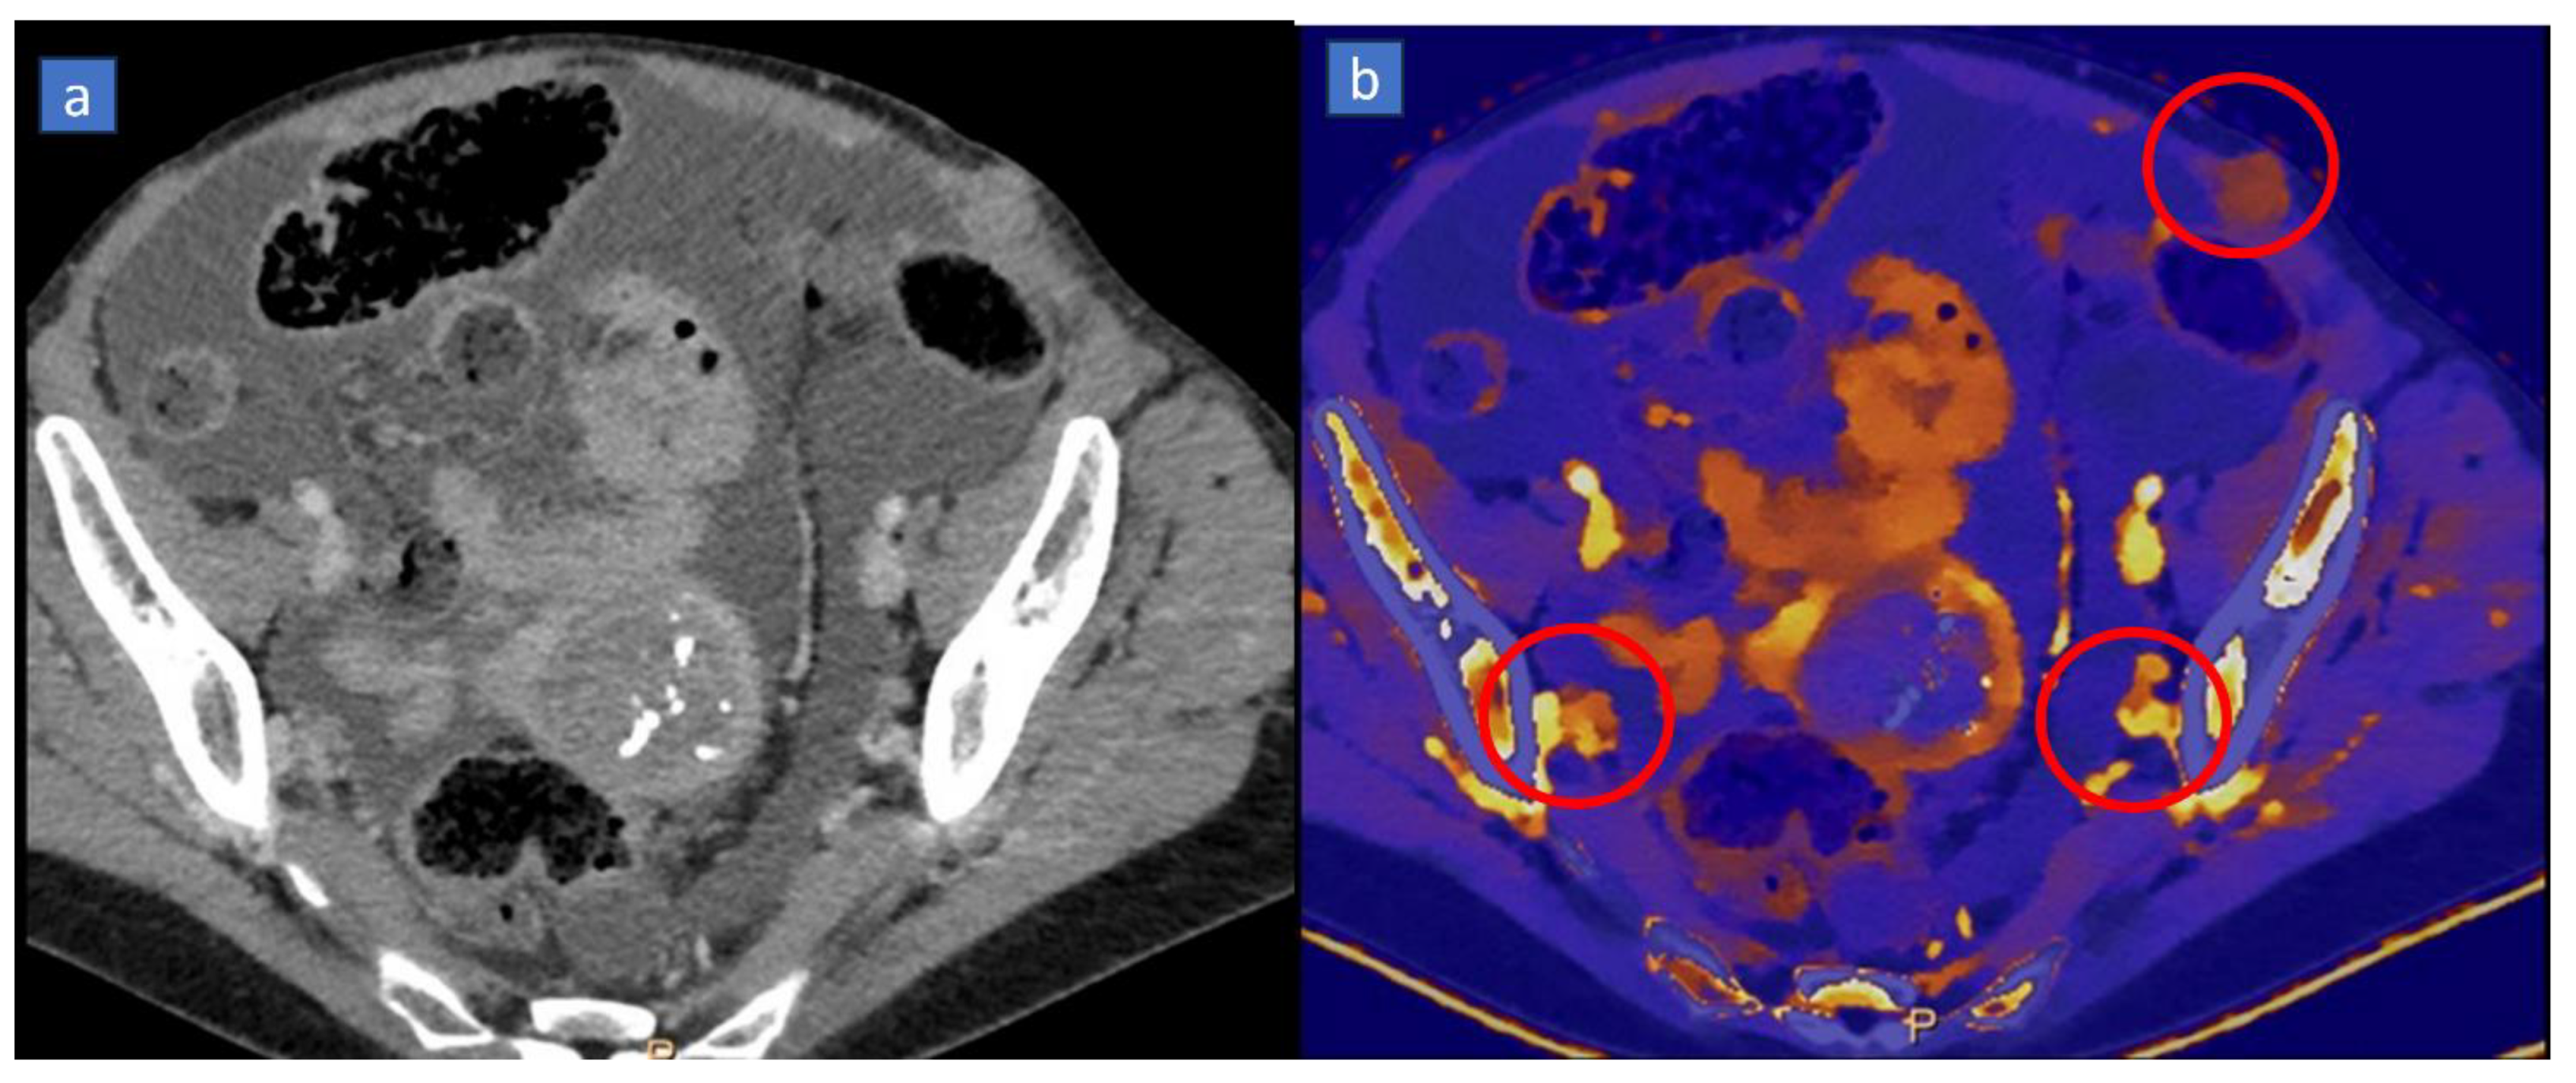

5. Bone Marrow Edema

Applications